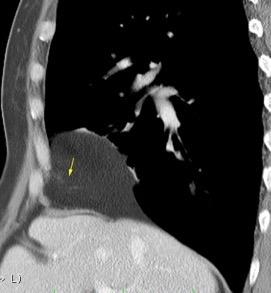

31. ENFERMEDAD TORACOABDOMINAL. TUMOR

Nódulos pulmonares múltiples. (flechas verdes). Masas paratraqueales. (flechas amarillas). Dudoso ensanchamiento retrocrural (flechas negras). sigue….

Ttawfik A et al. Trans-diaphragmatic Pathologies: Anatomical Background and Spread of Disease on cross-sectional Imaging. Current Problems in Diagnostic Radiology. 2021.

T. mixto de células germinales del testículo

izquierdo Metástasis pulmonares. (flechas verdes). Ganglios paratraqueales. (flechas amarillas). Ganglios retroperitoneales (flechas negras)

Tawfik A et al. Trans-diaphragmatic Pathologies: Anatomical Background and Spread of Disease on cross-sectional Imaging. Current Problems in Diagnostic Radiology. 2021.